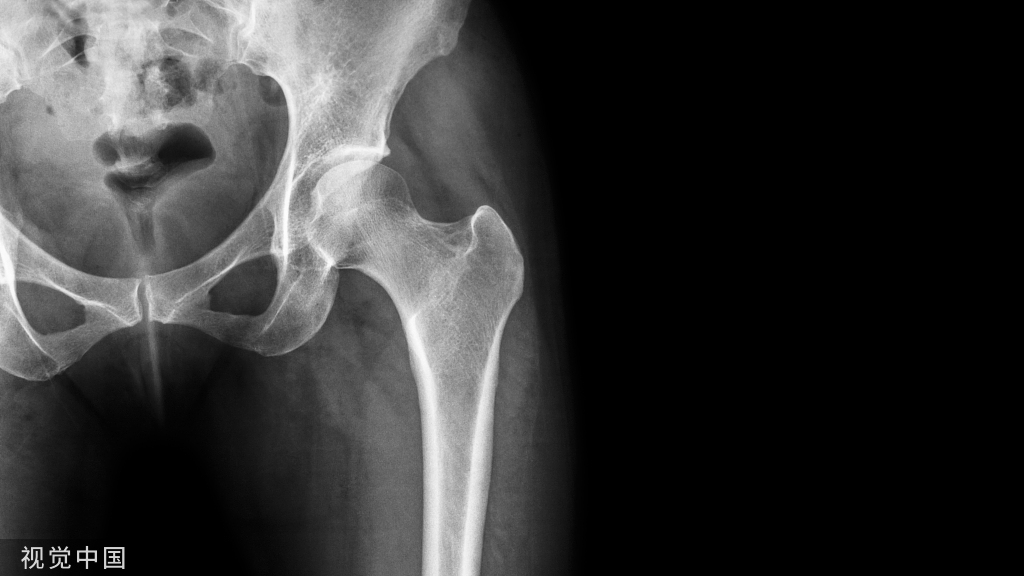

这是很多有膝关节疾病患者最想问的问题。对于他们来说,如果能根据膝关节疼痛的不同部位、疼痛的性质和程度,来进行区分,轻松知道自己膝关节是人体最复杂的一个关节,据统计,仅仅是膝关节炎的种类,就可以列出一百多种。膝关节里的任何一个零件出了问题都可能引发膝关节疼痛,而且很多膝关节疾病的症状交叉重叠,如果不借助临床查体和辅助检查,单凭症状很难鉴别。

好在有临床经验丰富的骨科医生已经为大家总结了6种膝盖异常所对应的疾病。在此,仅供参考,如果要明确诊断,当然还要在医生的诊室里进行。